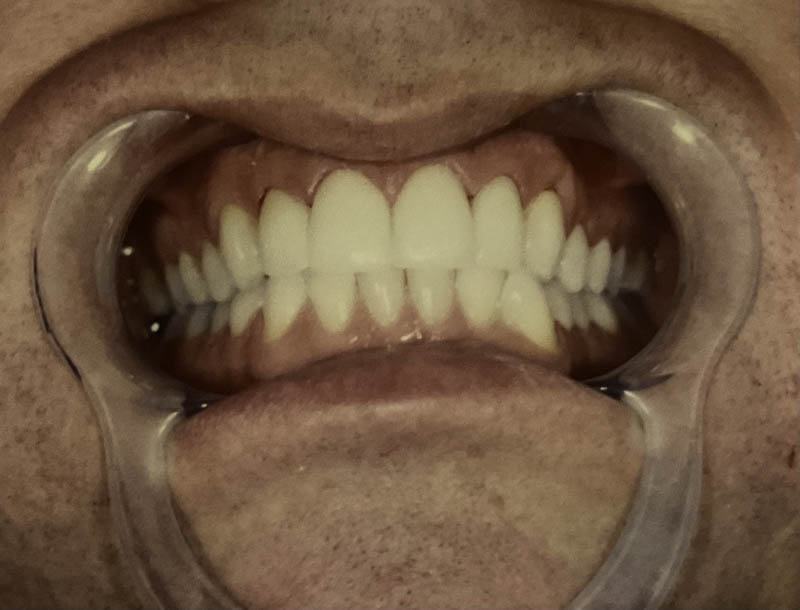

Before

After

Invisalign® Clear Aligners

Case Highlight